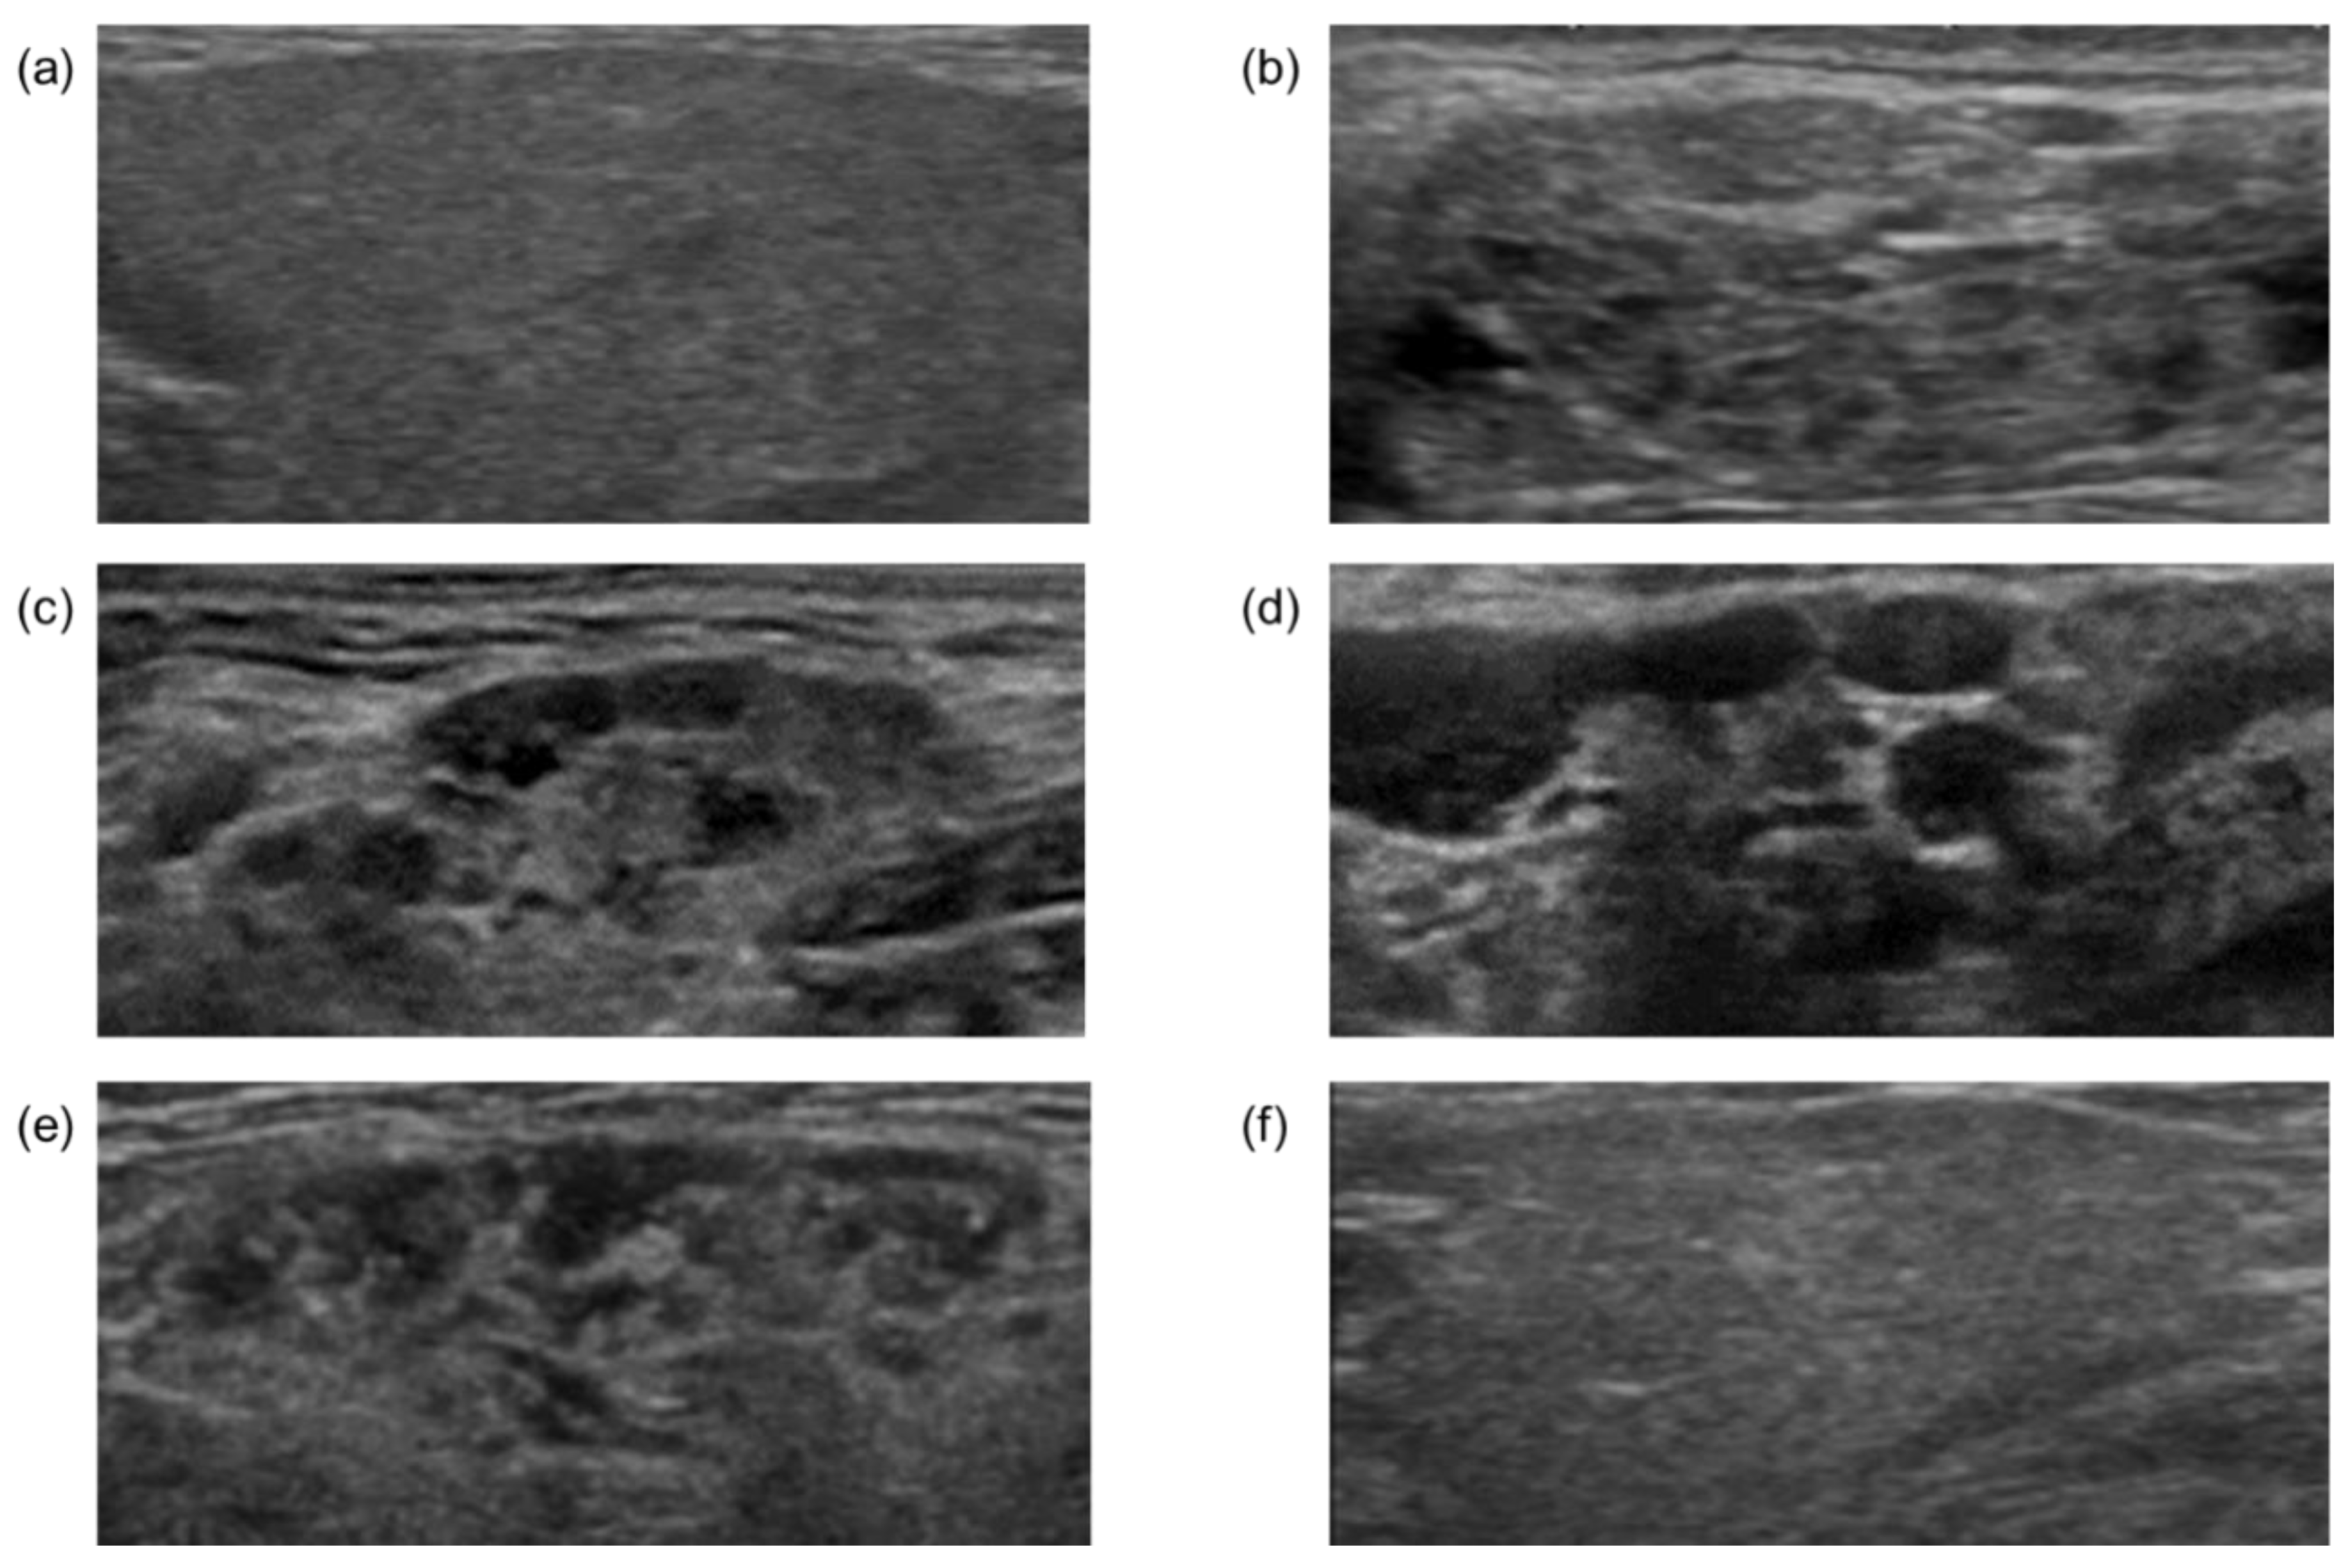

3.1. Patient Characteristics and Classification of US Findings in Submandibular Glands

3.5. A Representative Case in Which US Findings of SGs Might Be Useful